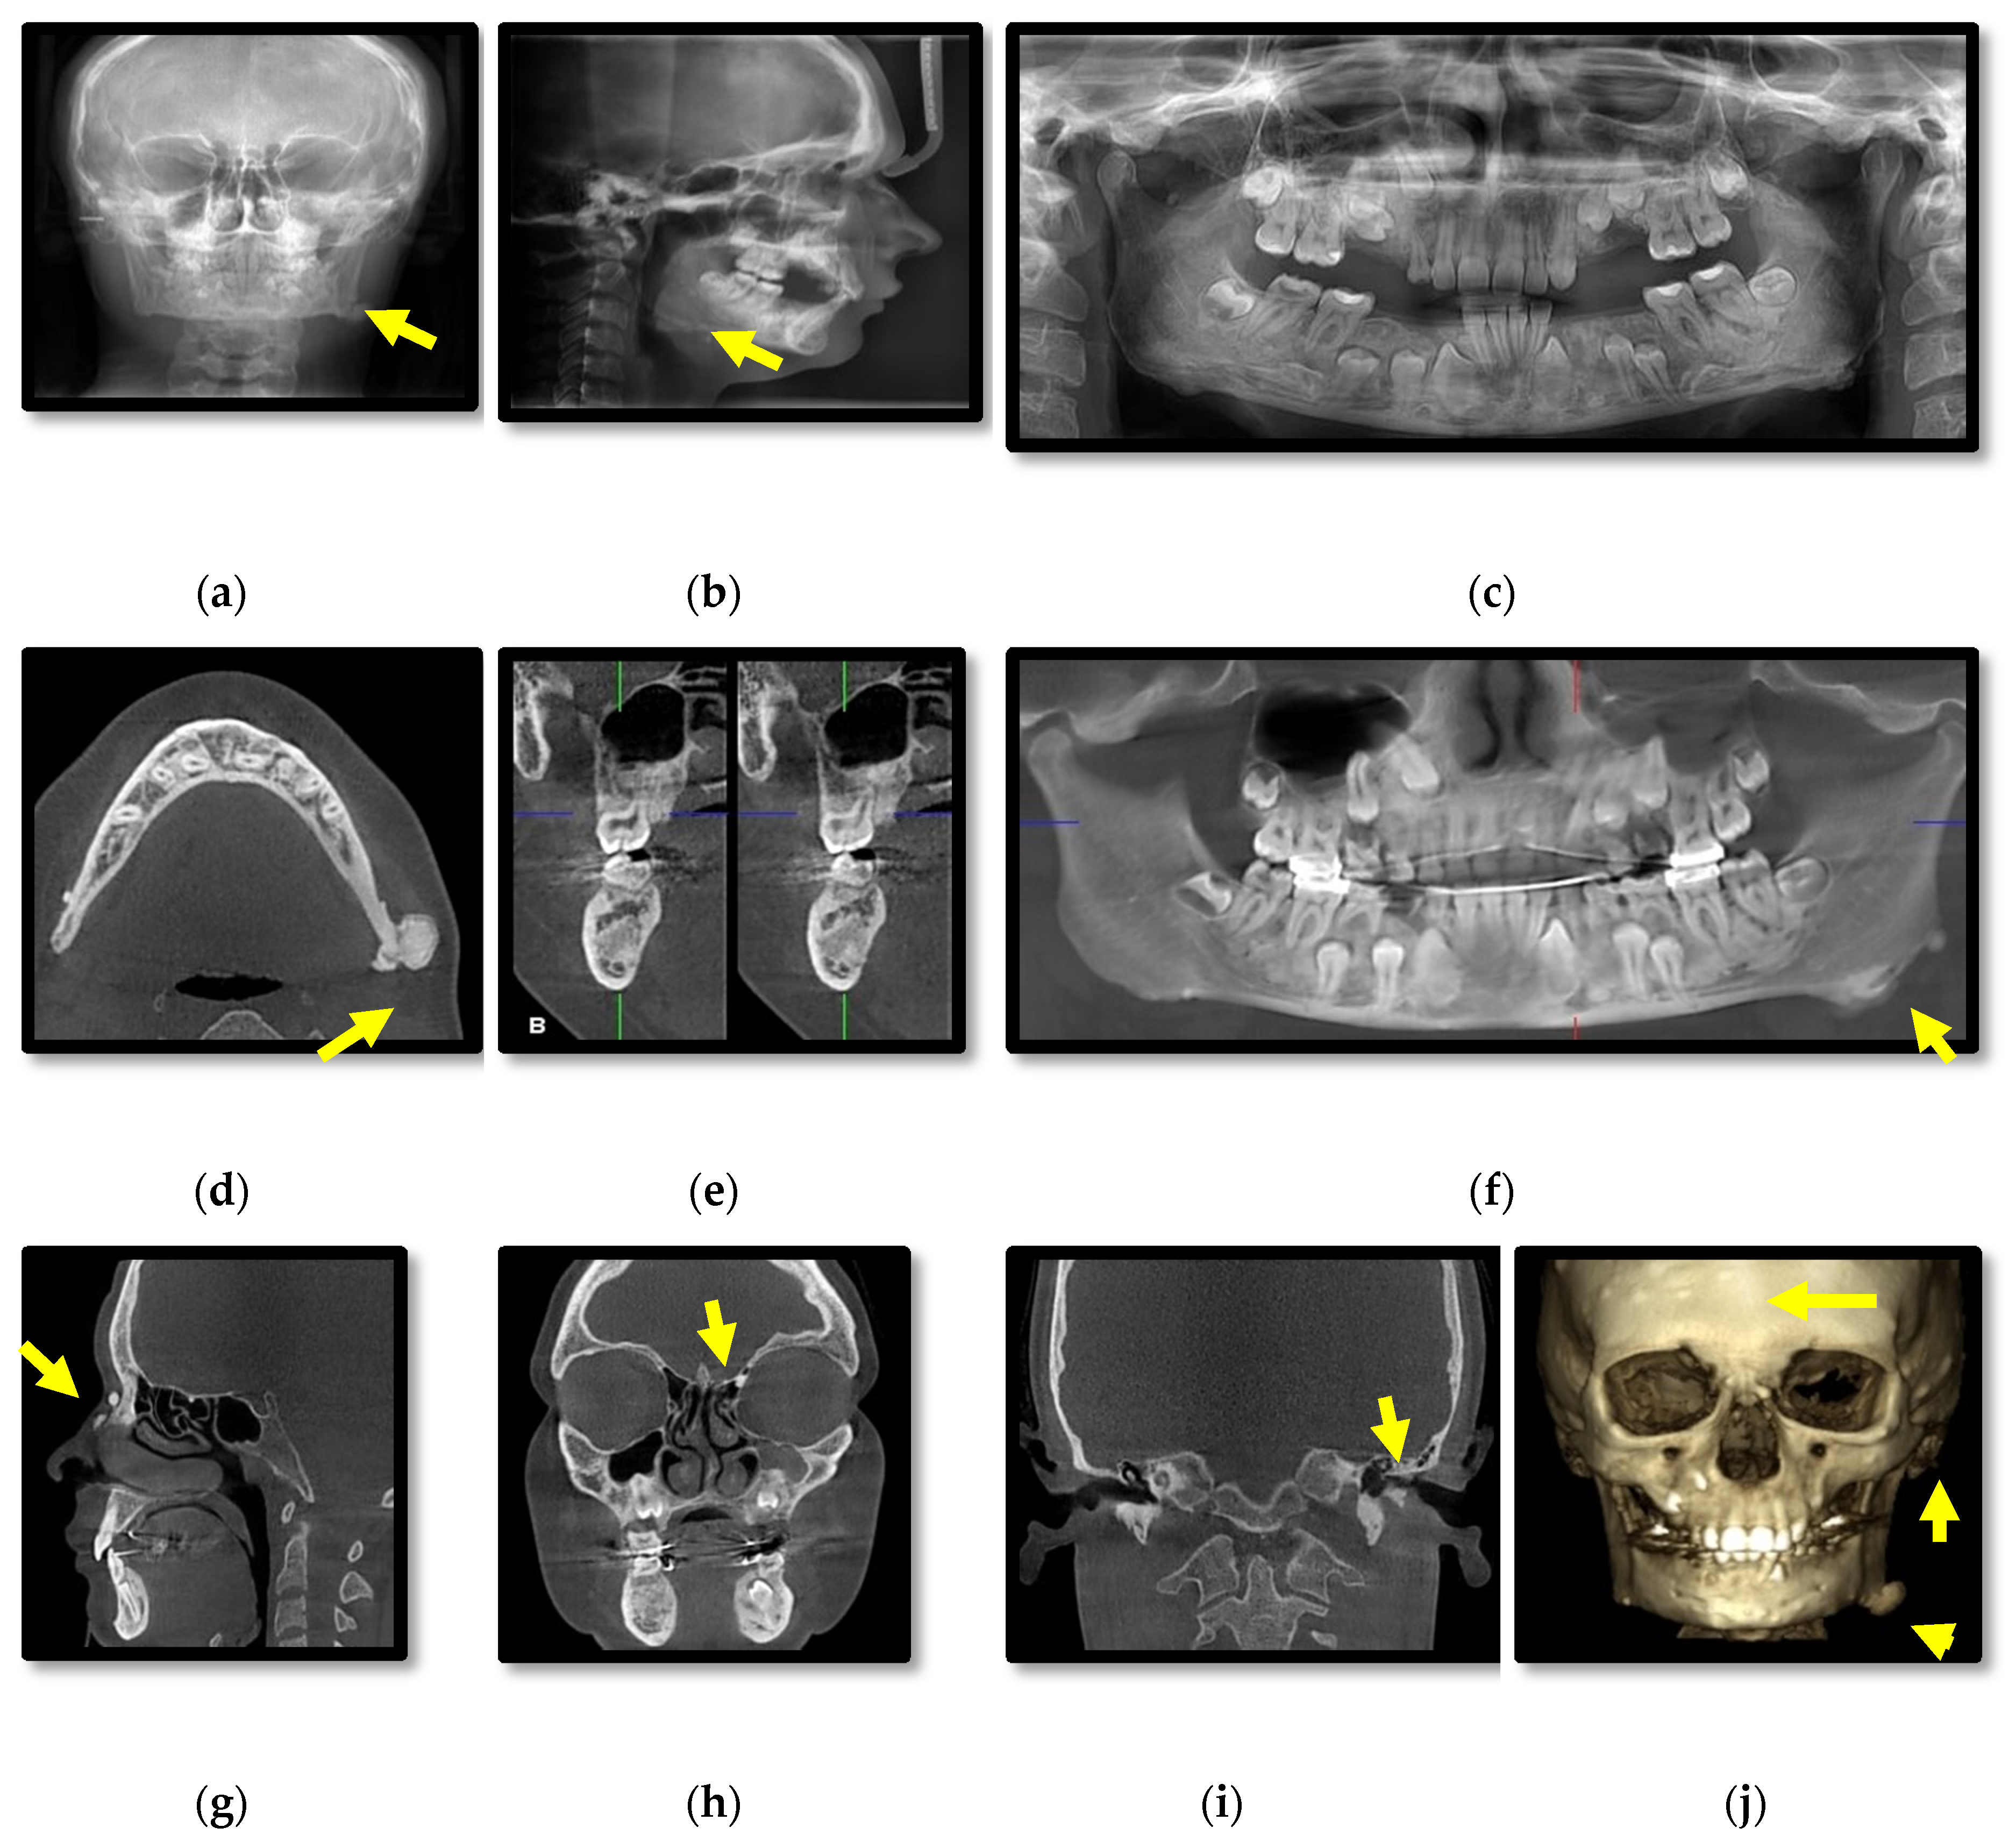

3.1. Radiographic Assessment

4.2. Osteomas

4.3. Dental Abnormalities